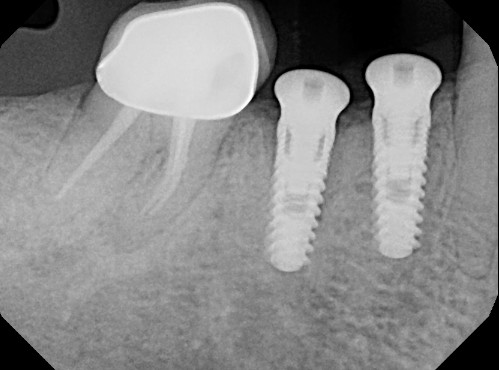

( after 3 months, implant was uncovered but the buccal cervical bone is missing , there is no denture use at all and the buccal wall just disappeared. there was no bone graft or membrane used when the implant was placed)

at the end, Ethoss, beta-TCP was grafted and moulded around the implant to close again.

Ossification is a complex and sometimes unpredictable process. I think 10 weeks is a too soon for implant placement since the extraction socket hasn’t fully calcified and you still have spongy bone inside the socket and psuedoperiosteum on the occlusal of the socket. I noticed radiographically i can see still see the socket. I usually enter and place implant at 4 months minimum post extraction, ideally 6 months, when radiographically the socket is mostly radiopaque indicating more calcification and ridge remodeled consistent to final dimensions.

I also noticed at implant placement i see 2 occlusal defects mesial and distal of the implant (most likely indicating mesial and distal root of previously extraction). which indicated the ridge is not fully ossified or calcified. i wonder if during osteotomy you felt soft bone instead of the usually hard mandibular bone. i think at implant placement you should have grafted. the occlusal is kind of flat, as if you did some occlusal reduction of some kind.